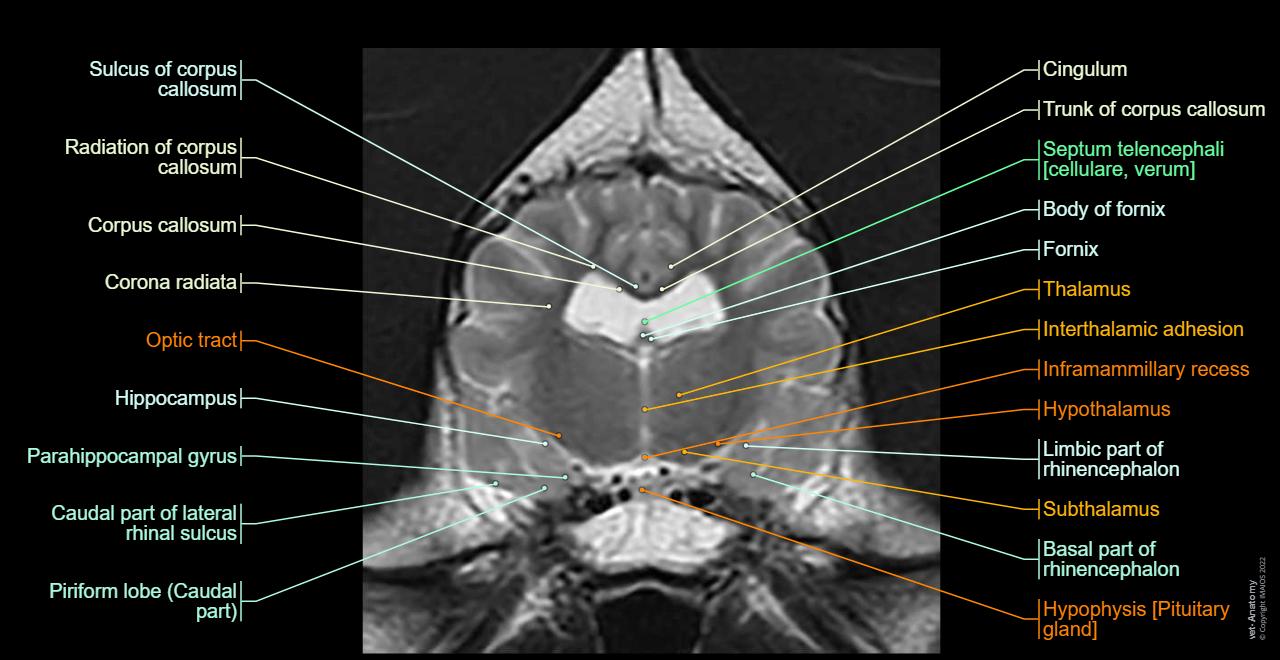

skulls too small for normal brain volume

compressed neurologic structures

skull shapes that crowd brain tissue